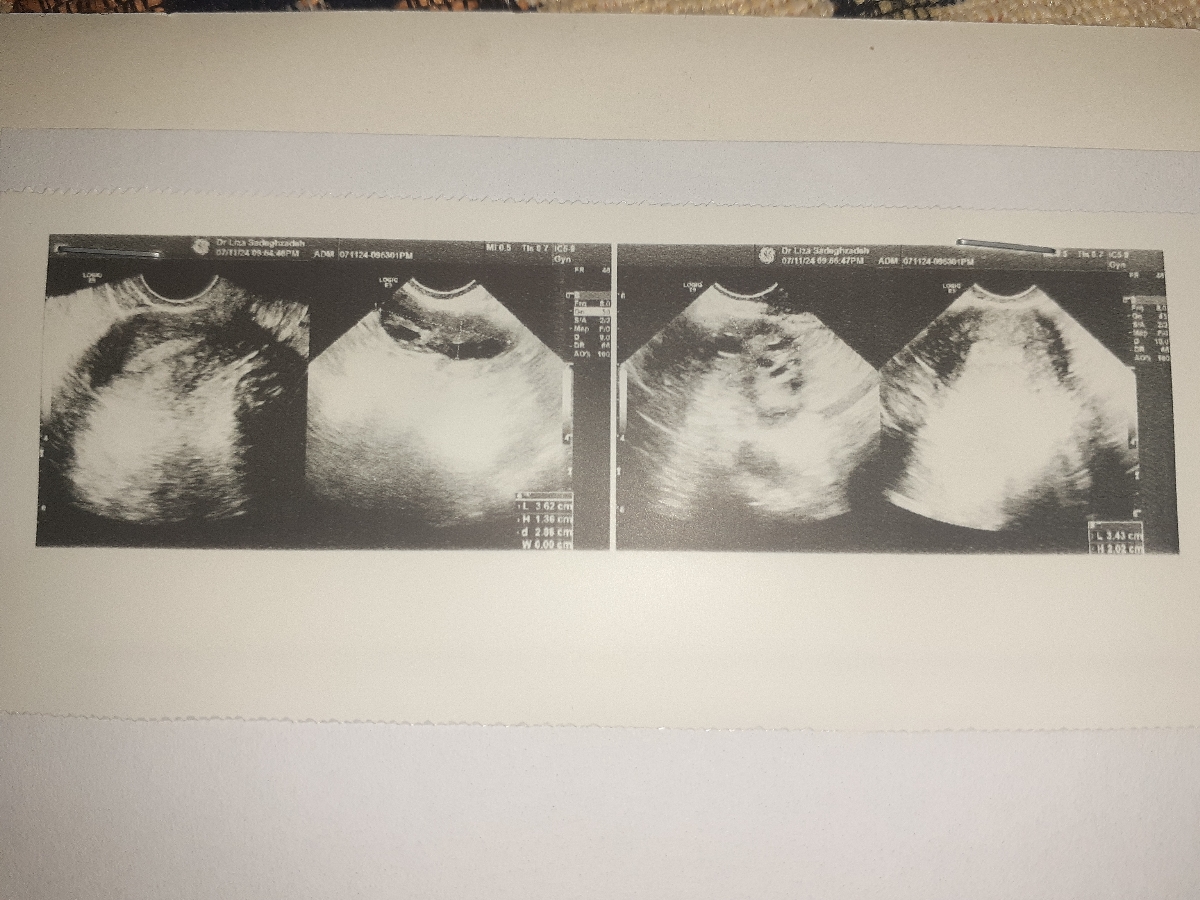

تو سونو واژینال pco یا همون تنبلی تخمدان گزارش شده

اینم سونوگرافی رحم تخمدان تست پاپ اسمیر اچ پی وی و آزمایشات قبل بارداری